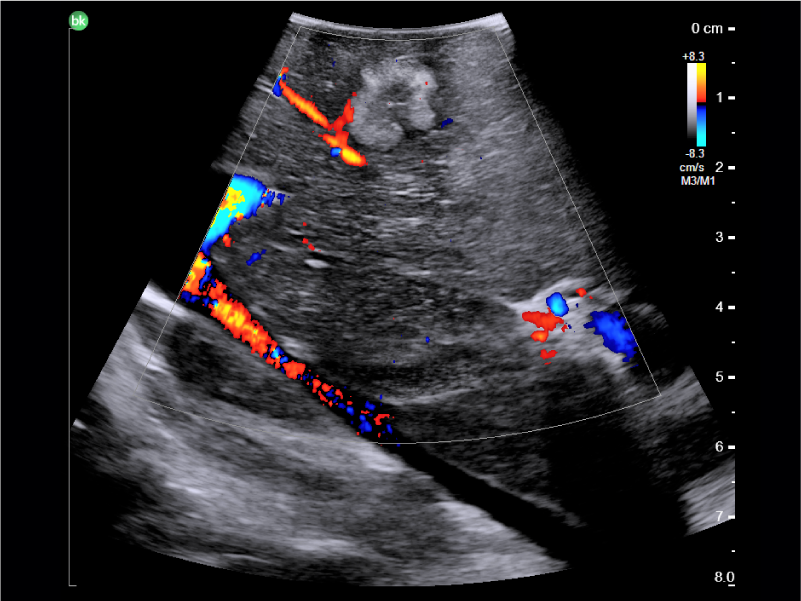

Liver metastatic lesion with color Doppler, visualized with Laparoscopic Transducer

Active imaging with intraoperative ultrasound supports critical decision-making in open or minimally invasive tumor resections.

• Enable visualization of disease staging at the time of surgery with excellent image quality

• Visualize complex anatomical variations and identify tumor location

• Define adequate margins of resection

• Guide and view needle placements

• Assess surgical planning and check for vessel patency at the end of the procedure